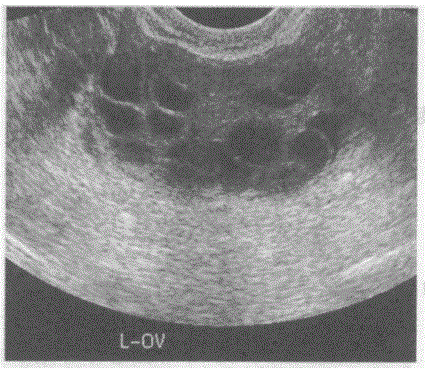

问题 临床资料:女,29岁,自述自幼肥胖,多毛,月经稀少,结婚5年不孕。 化验检查:雄激素与睾酮升高。 超声综合描述:经阴道扫查,子宫小,内膜显示不清;双侧卵巢均匀性增大。包膜光滑增厚回声增强,每个超声切面可见>10个大小不等无.回声区,最大直径0.9cm,透声清亮。 超声提示:

选项 A.多囊卵巢综合征 B.葡萄胎 C.卵巢过度刺激综合征 D.正常卵巢声像图

答案 A